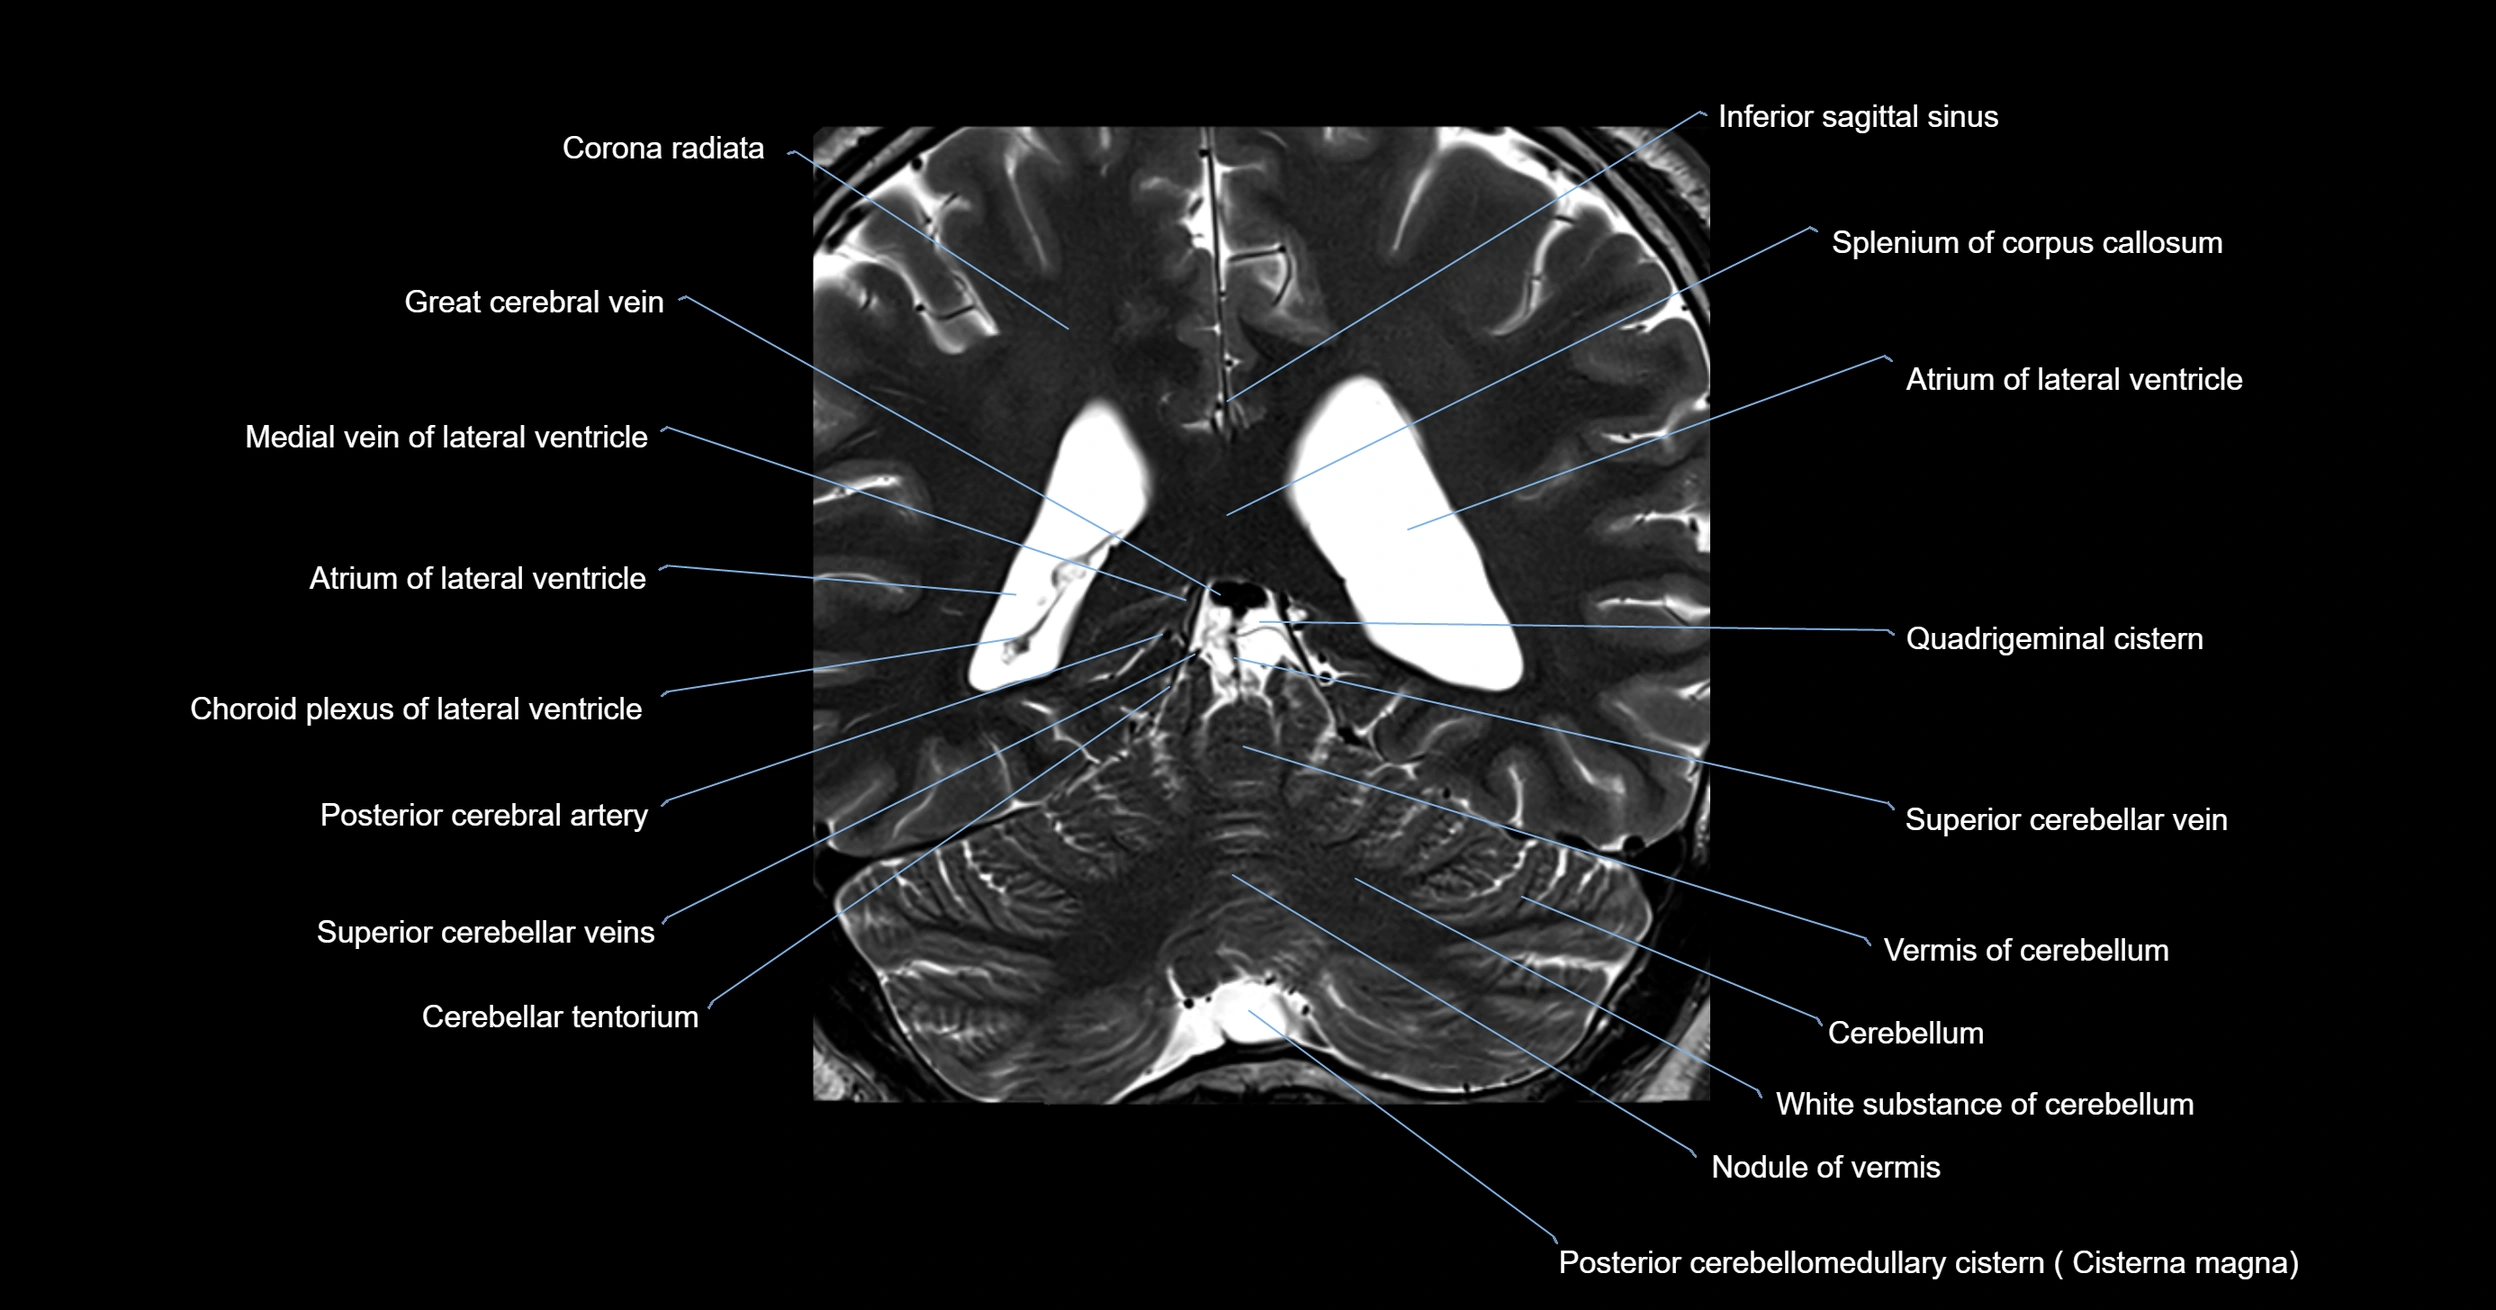

- Atrium of lateral ventricle

- Cerebellar tentorium

- Cerebellum

- Corona radiata

- Crus of fornix

- Great cerebral vein

- Medial vein of lateral ventricle

- Nodule of vermis

- Posterior cerebellomedullary cistern (cisterna magna)

- Posterior cerebral artery

- Splenium of corpus callosum

- Superior cerebellar vein

- Vermis of cerebellum

- White matter of cerebellum (Arbor vitae)

- White substance of cerebellum